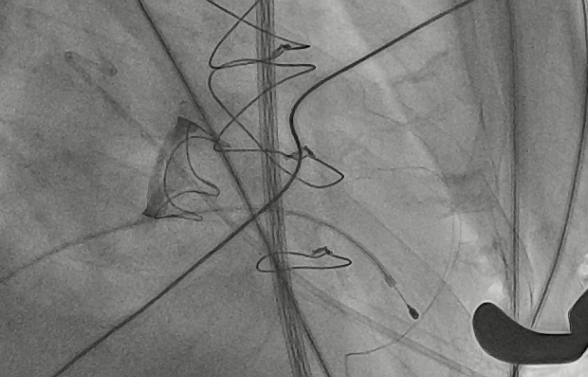

CDFI提示过瓣血流通畅

CDFI示少量瓣周漏

收缩期未见瓣周漏

左房内未见对比剂显影